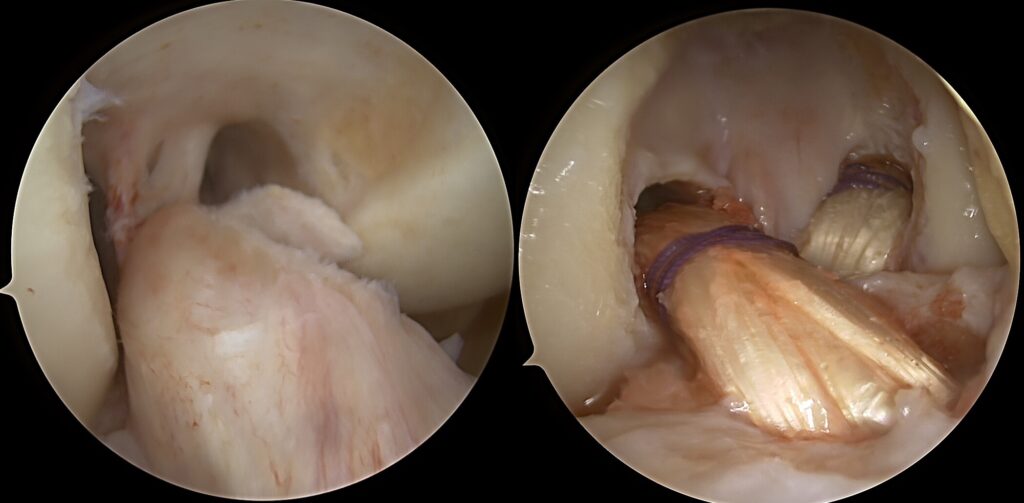

✔️ Priekinio kryžminio raiščio (ACL) ir užpakalinio kryžminio raiščio (PCL) rekonstrukcija – atstato priekinį ir užpakalinį stabilumą

✔️ Posteromedialinio nestabilumo rekonstrukcija – būtina apsaugoti kryžminius raiščius nuo pakartotinio nepakankamumo

✔️ V formos MCL ir POL rekonstrukcija – atkuria vidinį stabilumą ir rotacinę kontrolę

👉 V formos rekonstrukcija leidžia tiksliai atkartoti natūralią raiščių anatomiją, sumažinti liekamąją nestabilumo riziką.